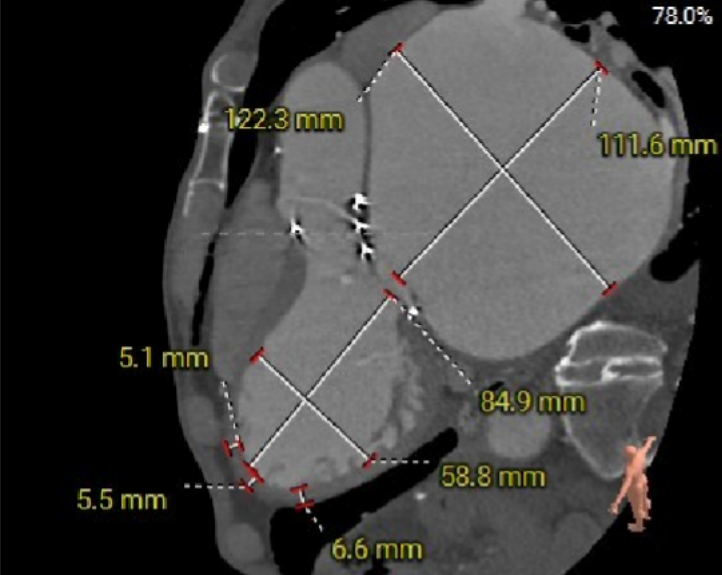

Annulus——内径

Annulus——外径

瓣架高度

LVOT

瓣上2mm

瓣上4mm

瓣上10mm

瓣上14.6mm

Sinotubular Junction

Ascending Aorta

SOV Diameter

Hockey Puck (VR)

LCA Height

RCA Height

选瓣依据:该主动瓣原置换生物瓣为Hancoke II#25,CT测量生物瓣瓣环周长折算直径约22.8mm,瓣架高度约18.0mm;